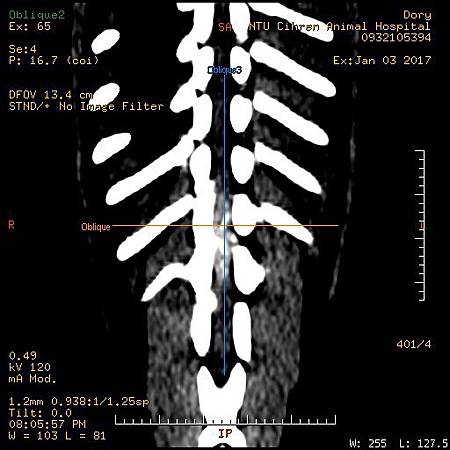

斷層掃瞄 GE Brivo 385 全新16切

本院斷層掃瞄病患

1. 臘腸 IVDD椎間盤突出

3. 臘腸IVDD 椎間盤突出